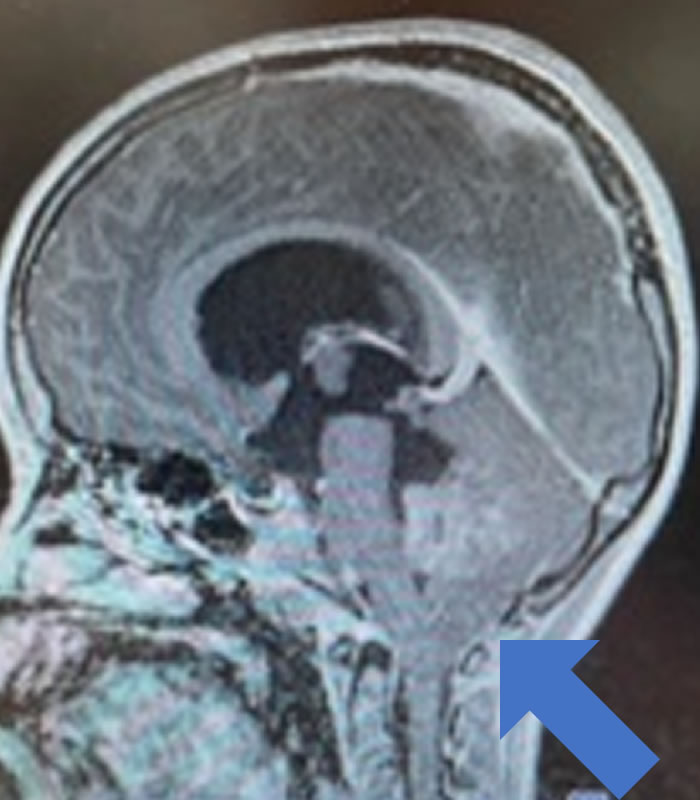

図1:胎児水頭症

図1:妊娠後期に見つかった胎児水頭症のMRI撮影です。母親の母体内の様子を観察しております。胎児は動きがあるので、特別な撮影条件が必要です。